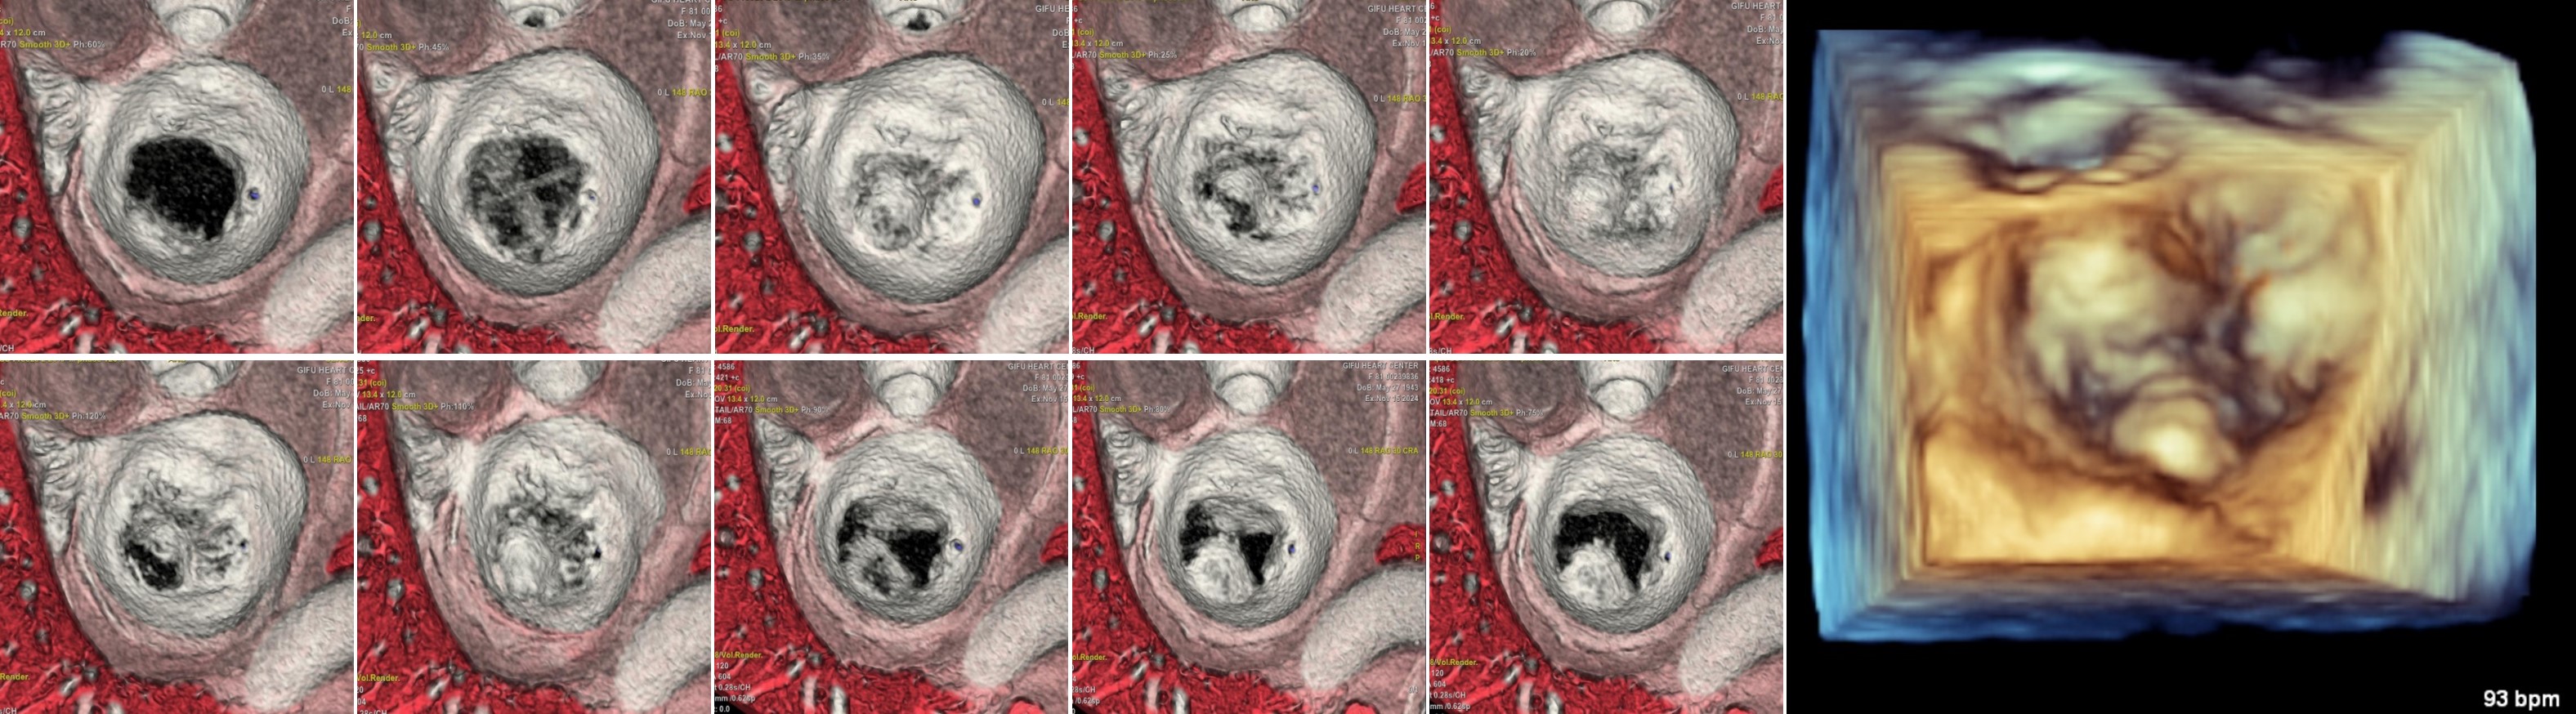

◆TAVI (Transcatheter Aortic Valve Implantation) 前

既存装置では R-R 10~30% の駆出期の静止画像を得ることが困難なケースが散見されました。従って、大動脈弁が最も開放している画像よりもモーションアーチファクトが少ない画像を選択しなければならないことが多く、R-R 25~40% 辺りの心位相で大動脈弁複合体の計測を行っていました。

しかし、SSF2.0 が導入されてからは0%から100%を5%刻みで再構成した上で最も大動脈弁が開いている心位相で弁計測 (真の最大弁輪径) することが可能になりました。

また、SSF2.0 の恩恵で弁の 4D 描写が可能となり、大動脈弁尖の石灰化癒合による二尖弁なのか高度石灰化による三尖弁かどうかが鑑別できるようになりました。TAVI を施行するにあたり二尖弁か三尖弁で計測方法や計測箇所も変わってくるため、弁観察における SSF2.0 の恩恵は実臨床においても大きいと実感しており、当院の医師からも安心して手技に挑めると評価をいただいています。

RevolutionCT_gifuheart04.jpg

Fig.3 二尖弁と鑑別できた大動脈弁4D画像